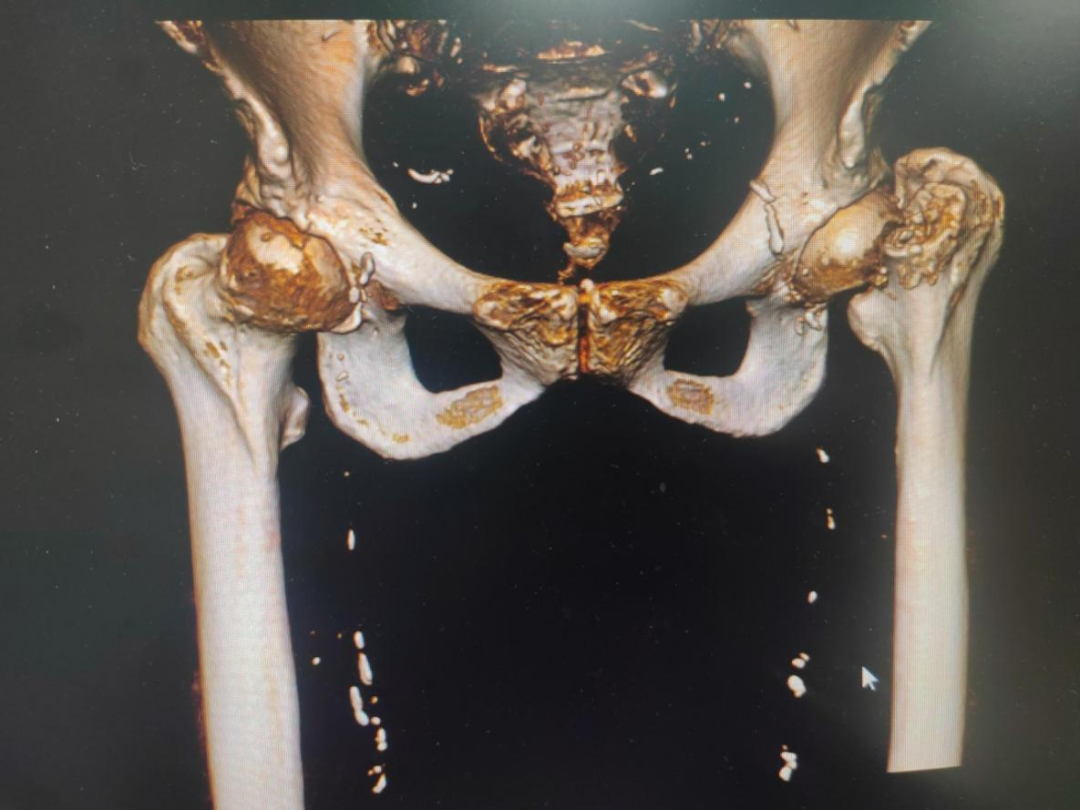

近日,近100歲高壽的潘奶奶,在家上廁所時(shí)不慎摔倒,導緻左股骨頸骨折(頭下型),其家屬急忙將(jiāng)潘奶奶送至惠州六院急診科。經(jīng)急診醫生初步評估後(hòu)轉送至惠州六院關節外科、運動醫學(xué)科病區,經(jīng)過(guò)術前檢查發(fā)現,潘奶奶左股骨頸骨折,又有重度骨質疏松症、雙側髋關節退行性變等20項病症。患者高齡,基礎疾病多,手術風險高。

8月15日,由關節外科、運動醫學(xué)科主任餘金勝主刀,帶領手術團隊成(chéng)功進(jìn)行左側人工股骨頭置換術,術中用時(shí)不到30分鍾成(chéng)功置入髋關節假體,整個手術用時(shí)約80分鍾,術中仔細止血,術中無需輸血。